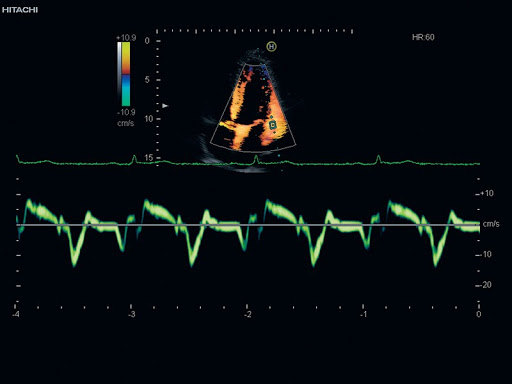

- Допплерография в режимах PW, B/PW, M/PW, B/M/PW, CW, B/CW, Fine Flow

- Цветное допплеровское картирование в режимах CFM-B, CFM-M, CFM-B/CFM-M, CFM-B/D, CFM-B/D/D, CFM-M/D, CFM-B/CFM-M/D

Тканевый допплер (TDI)